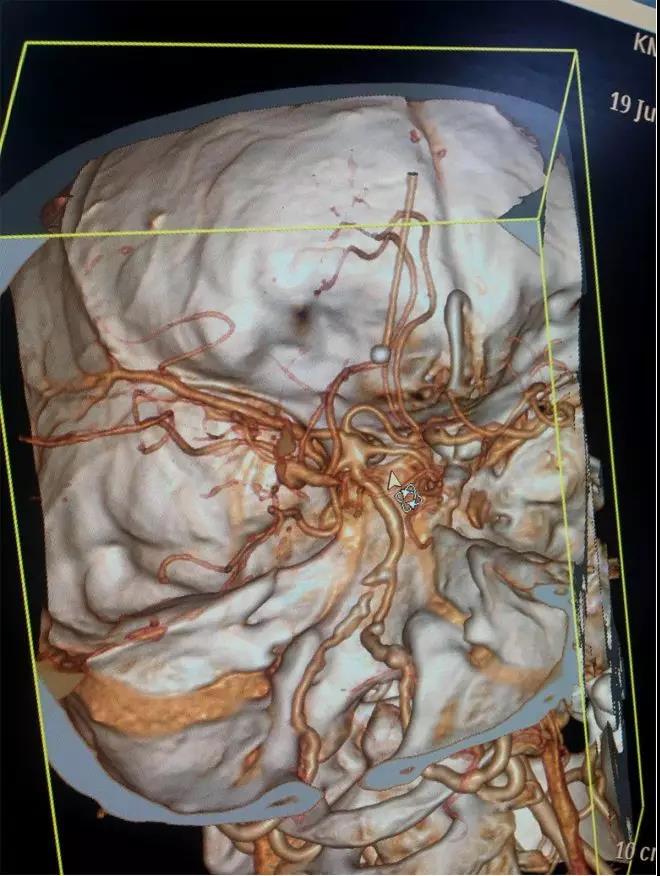

行头颈动脉CTA检查

DSA

右侧颈内动脉虹吸段夹层动脉瘤,右侧大脑前动脉A1段纤细